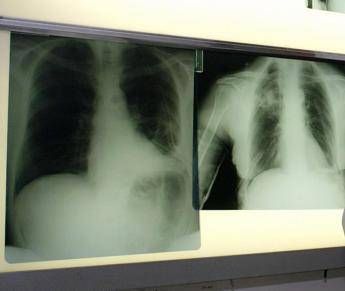

(Adnkronos) – La triplice terapia con budesonide/glicopirronio/formoterolo fumarato (Bgf), già autorizzata per il trattamento della broncopneumopatia cronica ostruttiva (Bpco) negli adulti, ha ricevuto parere positivo dal Comitato per i medicinali per uso umano (Chmp) dell’Agenzia europea per i medicinali (Ema) per l’utilizzo nell’Unione europea di un propellente innovativo di nuova generazione con un potenziale di riscaldamento globale (Gwp) prossimo allo zero. La triplice terapia con budesonide/glicopirronio/formoterolo fumarato è il primo farmaco somministrato tramite inalatore predosato pressurizzato (pMdi) a utilizzare un propellente green, con un potenziale di riscaldamento globale inferiore del 99,9% rispetto ai propellenti attualmente utilizzati nei farmaci inalatori. Questa triplice terapia a combinazione fissa avrà ora un impatto ambientale in termini di emissioni di carbonio comparabile a quella dei farmaci inalatori che non necessitano di propellente.

Le malattie respiratorie croniche, tra cui la Bpco e l’asma – ricorda AstraZeneca – colpiscono centinaia di milioni di persone a livello globale. I farmaci inalatori respiratori somministrati tramite pMdi rappresentano il 76% dell’utilizzo di inalatori a livello globale e contribuiscono per lo 0,04% alle emissioni globali di gas serra. Gli studi dimostrano che il maggiore impatto ambientale associato alle malattie respiratorie deriva dal mancato controllo della patologia e dal conseguente aumento della necessità di ricorrere a servizi sanitari. L’implementazione di linee guida basate sulla generazione di evidenze nella pratica clinica può contribuire a ridurre le riacutizzazioni e i ricoveri ospedalieri, migliorare gli outcome per i pazienti e anche diminuire l’impatto delle emissioni di carbonio complessive associate alle cure respiratorie.